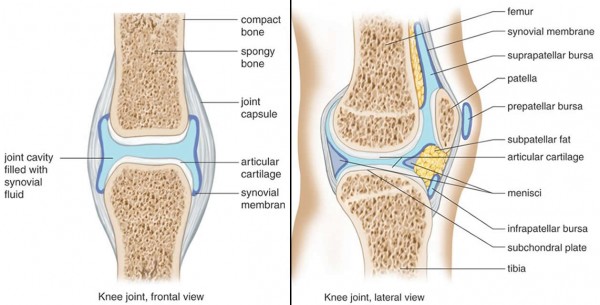

- Here’s some terminology and a diagram to help navigate the knee from the outside in.

- The joint capsule is soft tissue containing the synovium and synovial fluid.

- Synovium is the lining on the inside of the capsule that makes synovial fluid.

- Synovial fluid lubricates the joint and acts as a secondary shock absorber to the cartilage.

- Scarring results in a loss of range of motion that can result in joint capsule tightness.

- Improper functioning caused by joint capsule tightness may increase wear and tear on cartilage and other joint structures.

- In some cases, after the scarring has been ameliorated through surgery, joint capsule tightness will also need to be addressed.